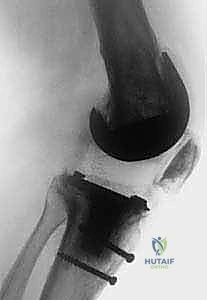

2. التصوير الشعاعي المتقدم: أشعة سينية (X-rays) بأوضاع خاصة لتقييم حجم المكونات وتثبيتها.

3. الأشعة المقطعية (CT Scan): وهي ضرورية جداً لقياس زوايا دوران المكونات المعدنية بدقة متناهية لا تظهر في الأشعة العادية.

قبل دخول غرفة العمليات، يتم دراسة الأشعة وتحديد نوع المفصل القديم، وتجهيز المكونات الجديدة التي تحتوي على أجزاء تعويضية (Stems and Augments) لتعويض أي نقص في العظام.

الخطوة الرابعة: إزالة المكونات القديمة بدقة

بأدوات متخصصة، يتم استخراج المكونات المعدنية والأسمنت العظمي القديم بحذر شديد للحفاظ على أكبر قدر ممكن من العظام السليمة للمريض.

الخطوة السادسة: تركيب المفصل الجديد المُخصص للمراجعة

يتم استخدام مفاصل مراجعة خاصة تحتوي على سيقان معدنية تمتد داخل العظم لزيادة الثبات، ووسائد بلاستيكية (Polyethylene) ذات تقييد أعلى لضمان استقرار الركبة ومنع خلعها. يتم تثبيت المكونات بالزوايا الصحيحة تماماً لضمان حركة سلسة.